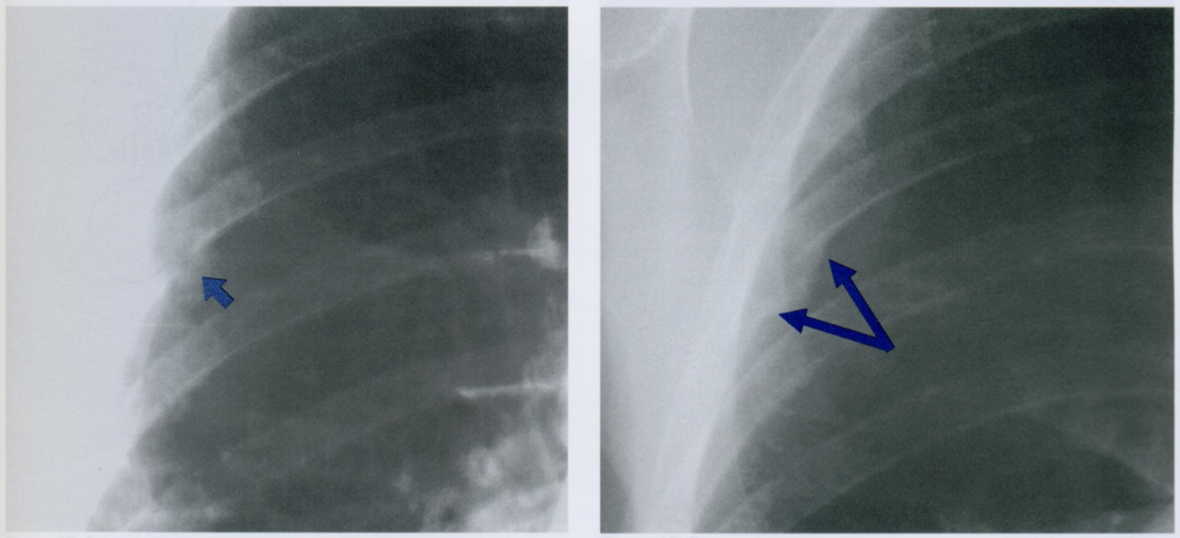

Оцените ассиметричность мягких тканей на снимке.

Обратите внимание на тень молочной железы (стрелочки), оцените симметричность теней слева и справа.

Ассиметрия прозрачности может наблюдаться после мастэктомий, радикального иссечения шейных лимфатических узлов, посттравматической гематомы грудной стенки, гепертрофии/атрофии мышц.

На данной карточке обратите внимание на просветления, отмеченные стрелками, которые свидетельствуют о наличии свободного воздуха в мягких тканях и средостении.

Признаки пневмомедиастинума:

1) эмфизема мягких тканей шеи

2) заметное просветление по контуру сердца или аорты, ограниченное снаружи париетальной плеврой (это то, что видно на данном снимке)

3) субкардиальное или ретрокардиальное скопление воздуха, четкая визуализация диафрагмы на всем протяжении

4) вилочковая железа у детей обнаруживается в виде «треугольного паруса» (у новорожденных - это норма)

5) пневмоторакс

6) пневмоперикард

7) воздух, окружающий ствол легочной артерии (в виде круга в боковой проекции)

На снимках воздух вдоль контуров сердца + воздух между волокон грудных мышц